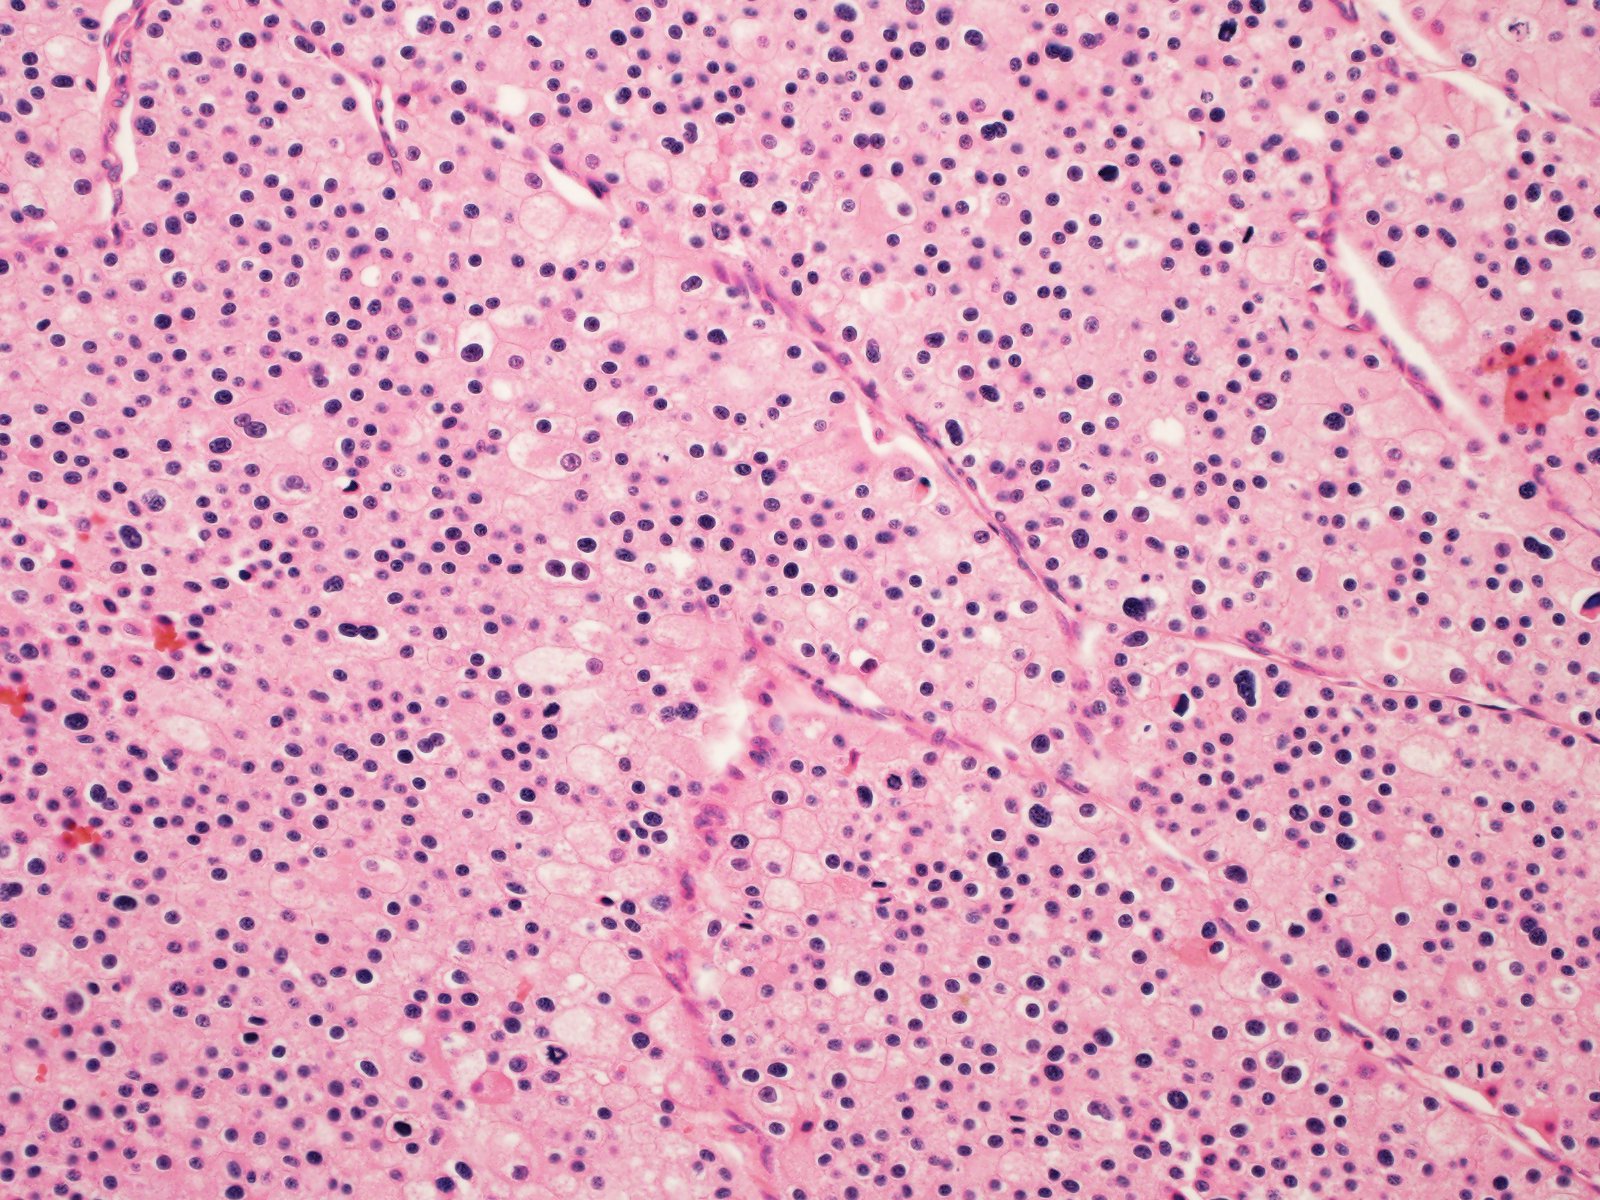

Case ID: 819

Consensus grade: I would not grade this tumor

chromophobe |

chromophobe RCC-grading? |

Case description (by case creator):